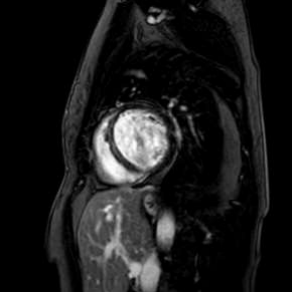

Cardiac magnetic resonance revealed left ventricle with characteristics of post-toxic cardiomyopathy and severely reduced global contractility with EF 34% (Image. 3- midmyocardial late gadolinium enhancement-LGE). Two chamber cine best visualized a cardiac mobile mass (11x7mm) attached to a small stalk to mid segment of the anterior wall of the left ventricle. The mass showed isointense signal on T1 (Image. 4), high intensity signal on T2 (Image. 5) and homogeneous late gadolinium enhancement (Image. 6). Characteristics were consistent with papillary fibroelastoma with differential diagnosis for myxoma or metastasis.

Image 6. CMR- homogeneous LGE of the intracardiac mass